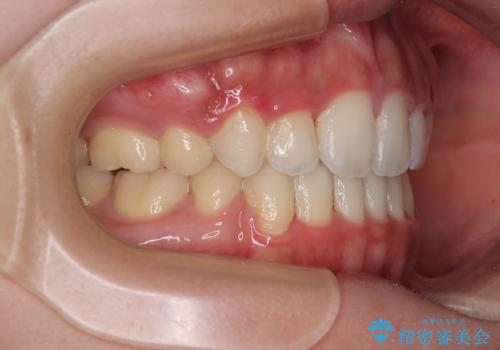

- 審美装置

- 1年10ヶ月

- 口元の突出感と口の閉じにくさを気にして来院された患者様です。

上下左右第一小臼歯4本を抜歯し、ワイヤー装置にて口元を引っ込めるよう矯正治療を行うこととしました。

口元の突出感が改善されてことで、下唇に引っかかっていた上顎前歯も気にならなくなりました。